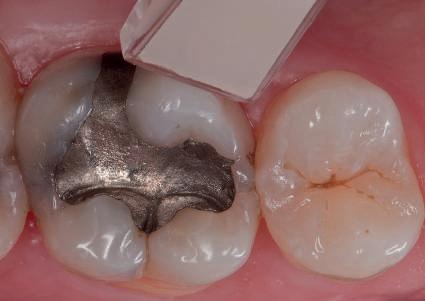

POSTERIOR COMPOSITES

Materialele compozite reprezintă un alt exemplu de proces revoluţionar al paradigmelor. Restaurările din silicat şi amalgam sunt aproape dispărute, în ciuda anumitor calităţi ce le caracterizează. Evoluţia spre compozite performante a fost facilitată de cercetările aprofundate ale proprietăţilor lor fizice, inovaţiile din acest domeniu avansând în paralel cu doleanţele estetice ale societăţii moderne.